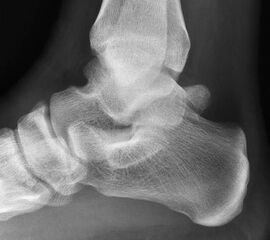

Reseziertes Os trigonum sowie prä- und postoperatives seitliches Röntgenbild nach arthroskopischer Entfernung eines Os trigonum.